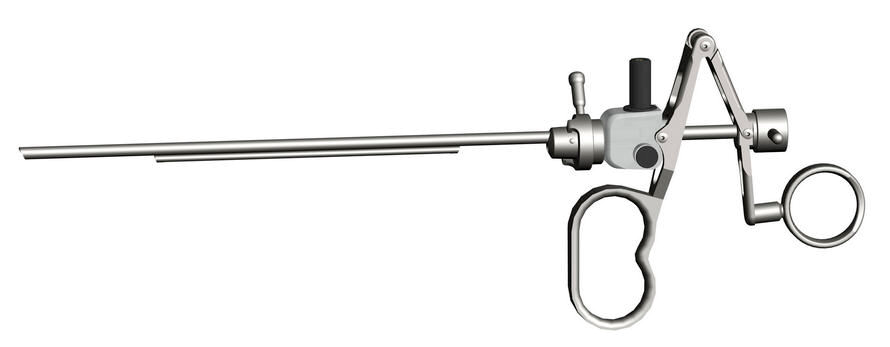

Obturador

Elemento de trabajo

- Corte mediante tensión de resorte.

- Anilla móvil para pulgar.

- Por seguridad, en posición de reposo, la punta del electrodo se encuentra dentro de la vaina.

Vaina de resectoscopio

- Vaina de resectoscopio de 26 Fr.

- Vaina interior con aislamiento de cerámica.

Cable de alta frecuencia o activo

Obturador

Elemento de trabajo

- Corte mediante tensión de resorte.

- Anilla móvil para pulgar.

- Por seguridad, en posición de reposo, la punta del electrodo se encuentra dentro de la vaina.

Vaina de resectoscopio

- Vaina de resectoscopio de 26 Fr.

- Vaina interior con aislamiento de cerámica.

Cable de alta frecuencia o activo

Llave de paso